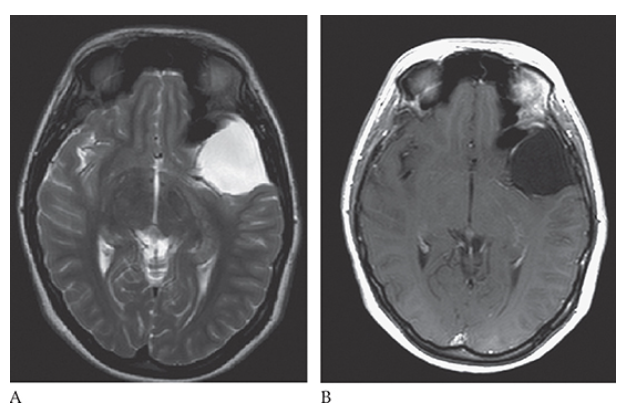

What is A

Dandy-Walker Syndrome. Axial T2W and coronal T1W

What is B

Dandy-Walker Syndrome. Axial T2W show absence of the cerebellar vermis.